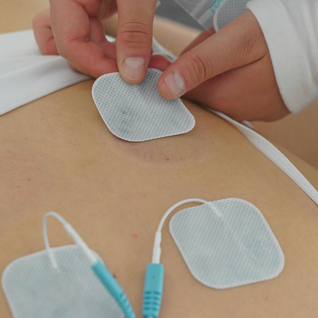

Eletroacupuntura

Como funciona: Utiliza correntes elétricas de baixa frequência para estimular os pontos de acupuntura através das agulhas inseridas, proporcionando estímulos por longo tempo.

Objetivo: Obter analgesia em casos de dores agudas, como hérnias de disco, e para tratamentos cirúrgicos.